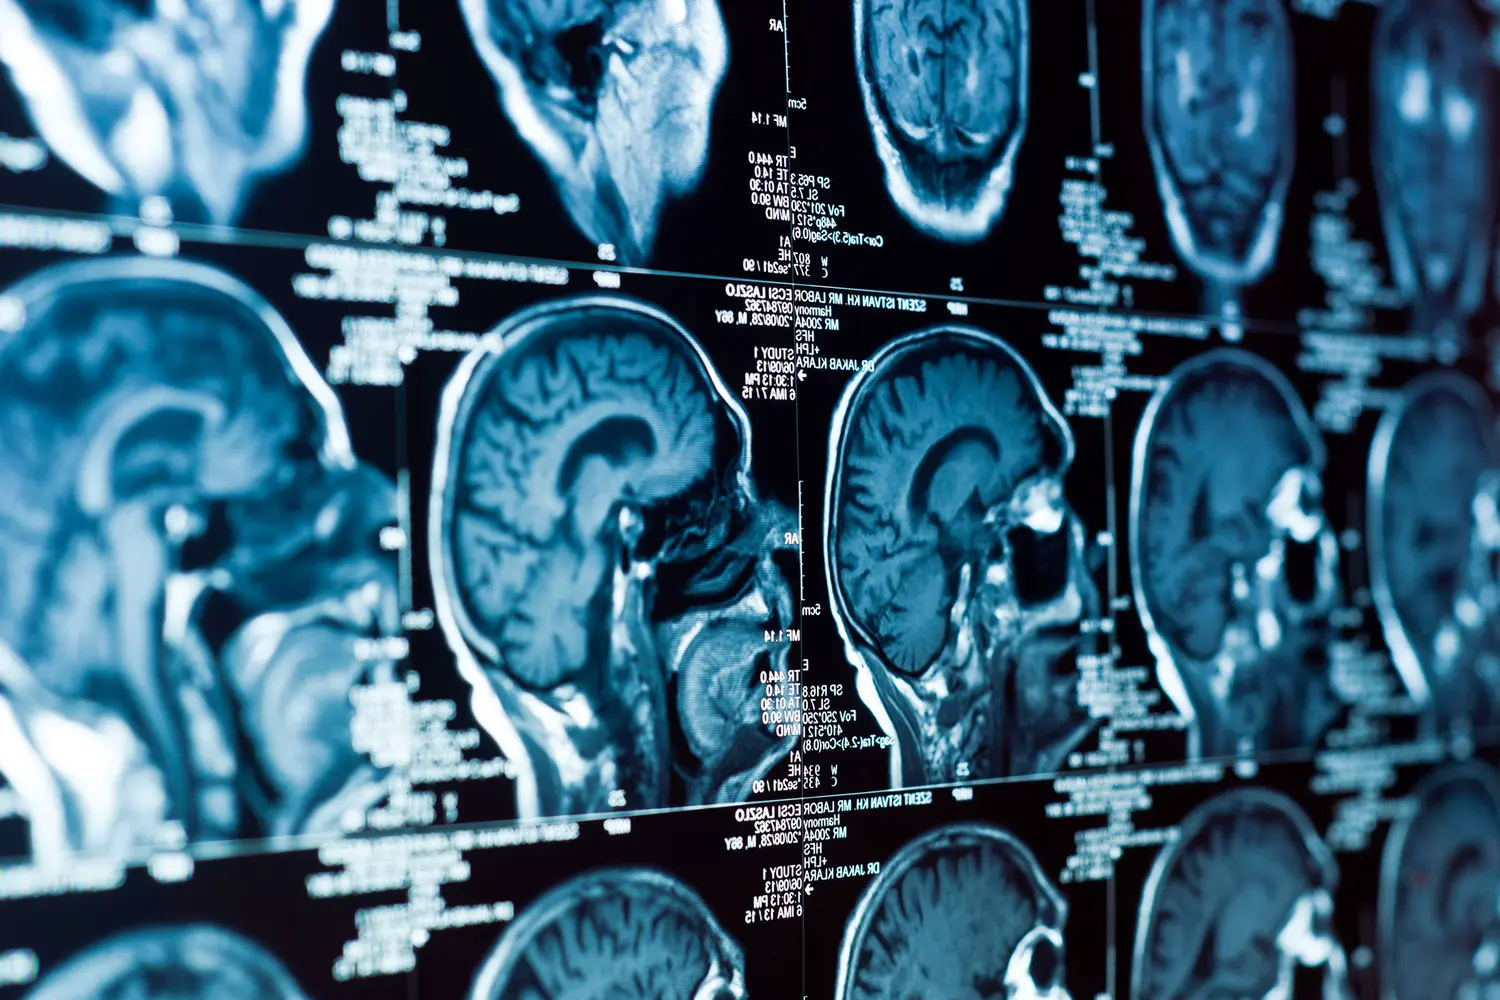

Найдено слабое место редкой детской опухоли мозга

Ученые Массачусетского технологического института обнаружили ключевую уязвимость эмбриональной опухоли с многослойными розетками (ETMR) — одного из самых агрессивных видов рака мозга у детей. Исследование показало: рост новообразования можно подавить, блокируя взаимодействие между двумя типами его клеток.